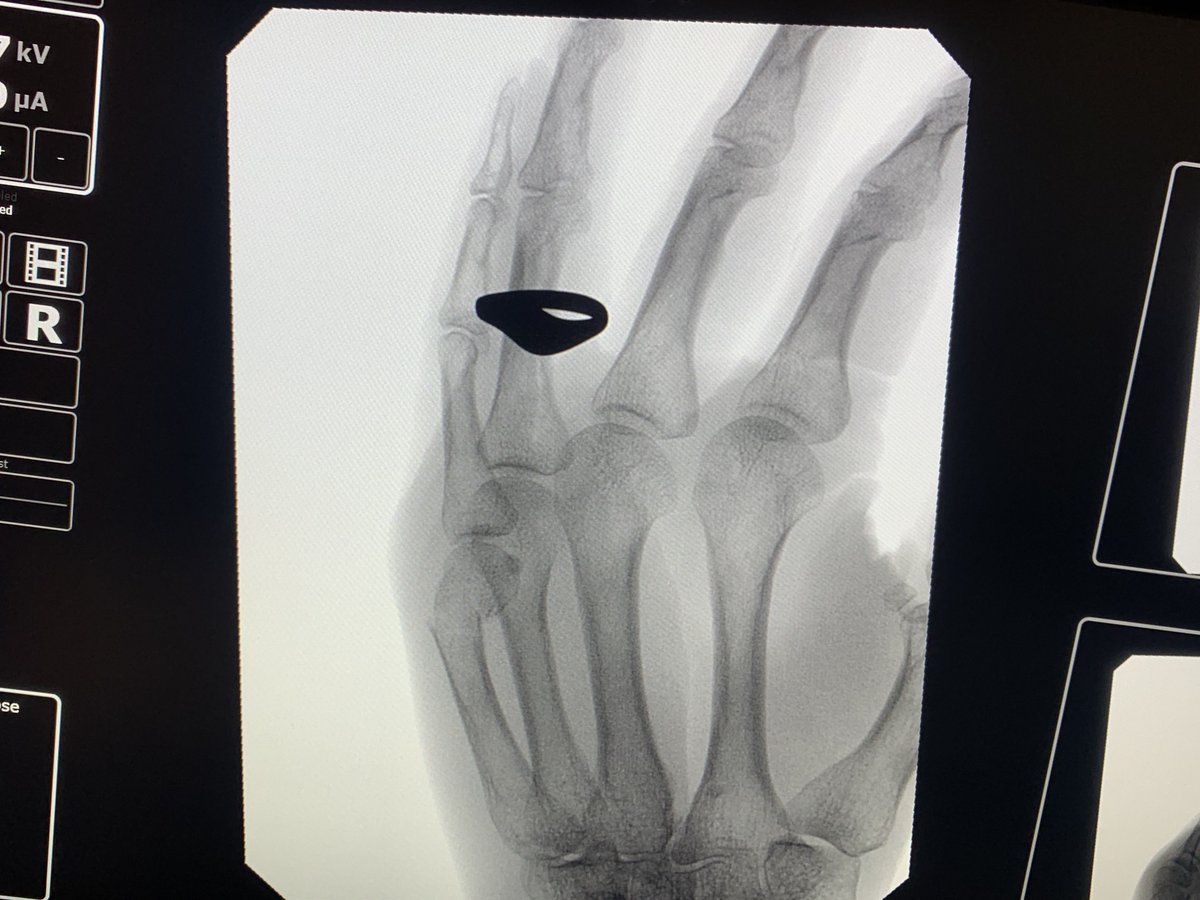

Boxer’s fracture, t + 4 weeks, and I get to remove the splint when sitting quietly. Hurray! Pinky finger only a little bit cockeyed

Boxer’s fracture, t + 18 days